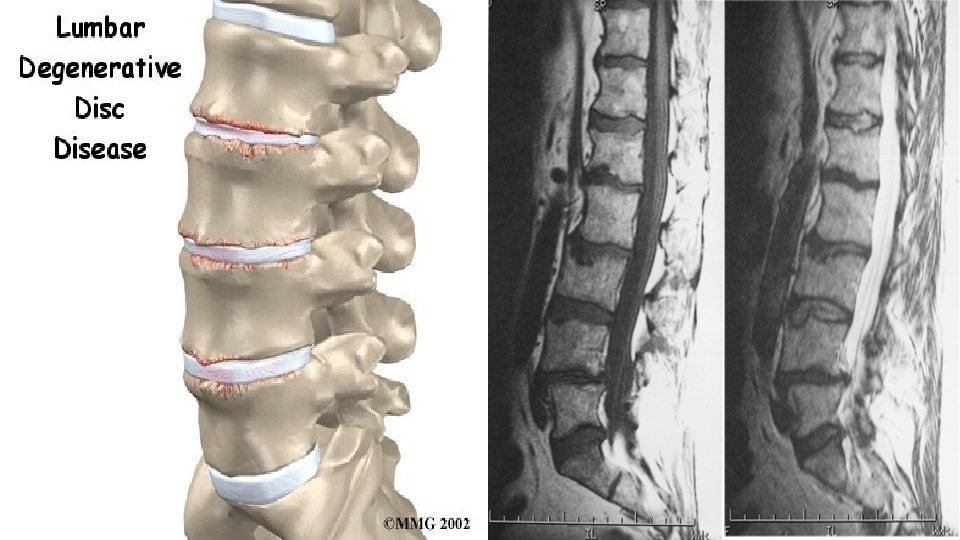

V. Обяснение на дегенерациите V. Explanation of degenerations